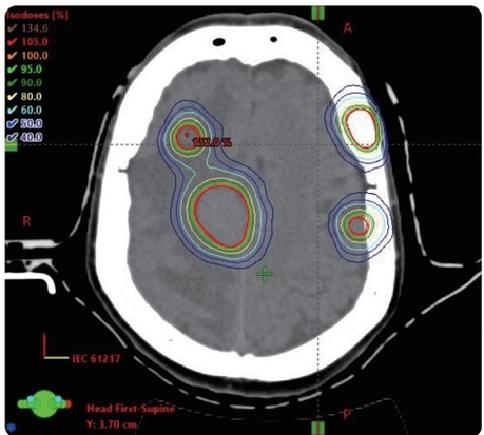

HyperArc technology

HyperArc is a non-coplanar stereotactic radiosurgery technology developed specifically for intracranial tumors. It has the characteristics of high precision, high efficiency and high automation. It has sub-millimeter accuracy and can complete the fixed-point radiosurgery treatment of several to dozens of brain metastases at the same time within 10 minutes, bringing better experience to patients with multiple brain me-tastases.

VMAT

HyperArc